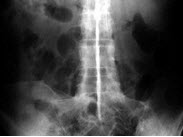

A.胰头

男,71岁,背部酸痛,低热,乏力,消瘦2月余,结合影像学表现,最可能的诊断是()

A.脊柱转移瘤

B.化脓性脊柱炎

C.脊椎结核

D.椎体压缩骨折

E.阻滞椎